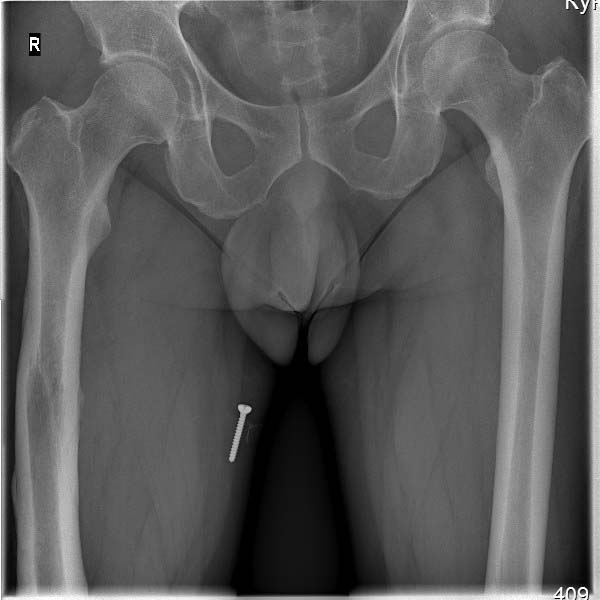

Пациент, мужчина, 45 лет. В 1982 году получил закрытый перелом диафиза бедренной кости

справа. Результат консервативного лечения-варусная деформация бедренной кости.

В 1987 году выполнена вальгусная корригирующая остеотомия на уровне дистального эпифиза

бедренной кости: варус бедренной кости нивелирован. Но в процессе лечения сформировалась

выраженная контрактура в правом коленном суставе. Производилось 2 раза агрессивная

разработка правого коленного сустава в аппарате типа Илизарова.